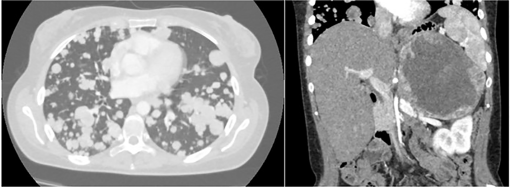

CT扫描证实巨大的左肾上腺肿块(大小为160x110mm),并显示肺部疾病显著进展,同时有多个肺转移病变( 图1 )。

图1. CT扫描(2020年1月)检测到多个肺转移病变和肾上腺肿块